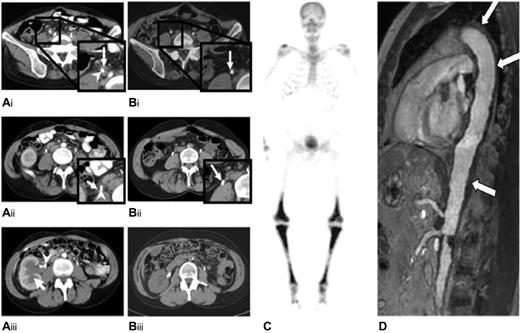

Abdominal computed tomography scans of patient 1 showed a regression of both bilateral fibrotic and stenosing periureteral infiltration and hydronephrosis 3 months after starting anakinra and then a complete disappearance of the infiltrates at 6 months of therapy (Figure 1A-B). Skeletal 99technetium scintigraphy showed a complete disappearance of the previously observed sites of increased uptakes, which had slightly persisted after cladribine treatment, but X-ray lesions on the leg bones remained unaltered. Kidney function returned to normal, and patient 1 stopped anakinra at month 11 on her own initiative because she felt improvement. She subsequently suffered a fever after 10 days off treatment; anakinra restart was allowed, and the patient again had a rapid and complete disappearance of fever. She remained well, and ureteral stents were withdrawn at month 18. She eventually decided on her own to stop the treatment at month 25. At month 32, she started to suffer recurrent mild and intermittent leg pains that were well controlled with paracetamol but had no fever spikes. Treatment with anakinra was reinstituted at month 36 with the same response.

Radiologic findings in patients 1 and 2. Abdominal computed axial tomography scan of patient 1, before (A) and after (B) anakinra. Before starting anakinra, a soft tissue mass was observed surrounding the right ureter (white arrow; A1, A2). Image A3 shows the dilatation of the right renal cavities (white arrow), which required the insertion of a JJ-ureteric catheter (white arrowhead). After 6 months of anakinra treatment, the retroperitoneal fibrosis surrounding the right JJ-catheter had disappeared (B1, B2; white arrow), and the kidney pyelo-ureteral cavities had returned to their normal sizes. (C) A 99m technetium-Methyl diphosphonate bone scan of patient 2 shows symmetrically increased uptake in the diaphyses and metaphyses of the femurs and tibias. (D) Magnetic resonance angiography of the aorta of patient 2 shows periaortic fibrosis (white arrow) with a coated aorta appearance.

Patient 2 had a similarly good response with urologic involvement, leading to the withdrawal of the left ureteral stent. Ureteropyelography performed 10 months after anakinra onset found that the stenosis had totally subsided, but that some abnormalities persisted, including slight residual segmental ureteral hypotonia and dilatation. Conversely, no radiologic improvement was noticed on skeletal scintigraphy, and the periaortic infiltrate shown in Figure 1C-D, remained unchanged at months 8 and 11, respectively. On this basis, treatment with anakinra was continued, with 26 months of follow-up from its onset.